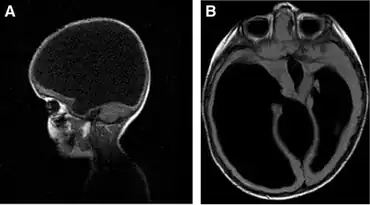

a) Sagittal b) and axial show severe congenital hydrocephalus

Hydranencephaly is a condition in which the cerebral hemispheres are missing and instead filled with sacs of cerebrospinal fluid. People are born with hydranencephaly, but most of the time, the symptoms appear in a later stage. Newborns with hydrancephaly can swallow, cry, sleep and their head is in proportion to their body. However, after a few weeks, the infants develop increased muscle tone and irritability. After a few months, the brain start to fill with cerebrospinal fluid (hydrocephalus). This has several consequences. Infants start to develop problems with seeing, hearing, growing, and learning. The missing parts of the brain and the amount of cerebrospinal fluid can also lead to seizures, spasm, problems with regulating their body temperature, and breathing and digestion problems. Besides problems in the brain, hydranencephaly can also be seen on the outside of the body. Hydrocephalus leads to more cerebrospinal fluid in the brain, which can result in an enlarged head.[9][10][11]